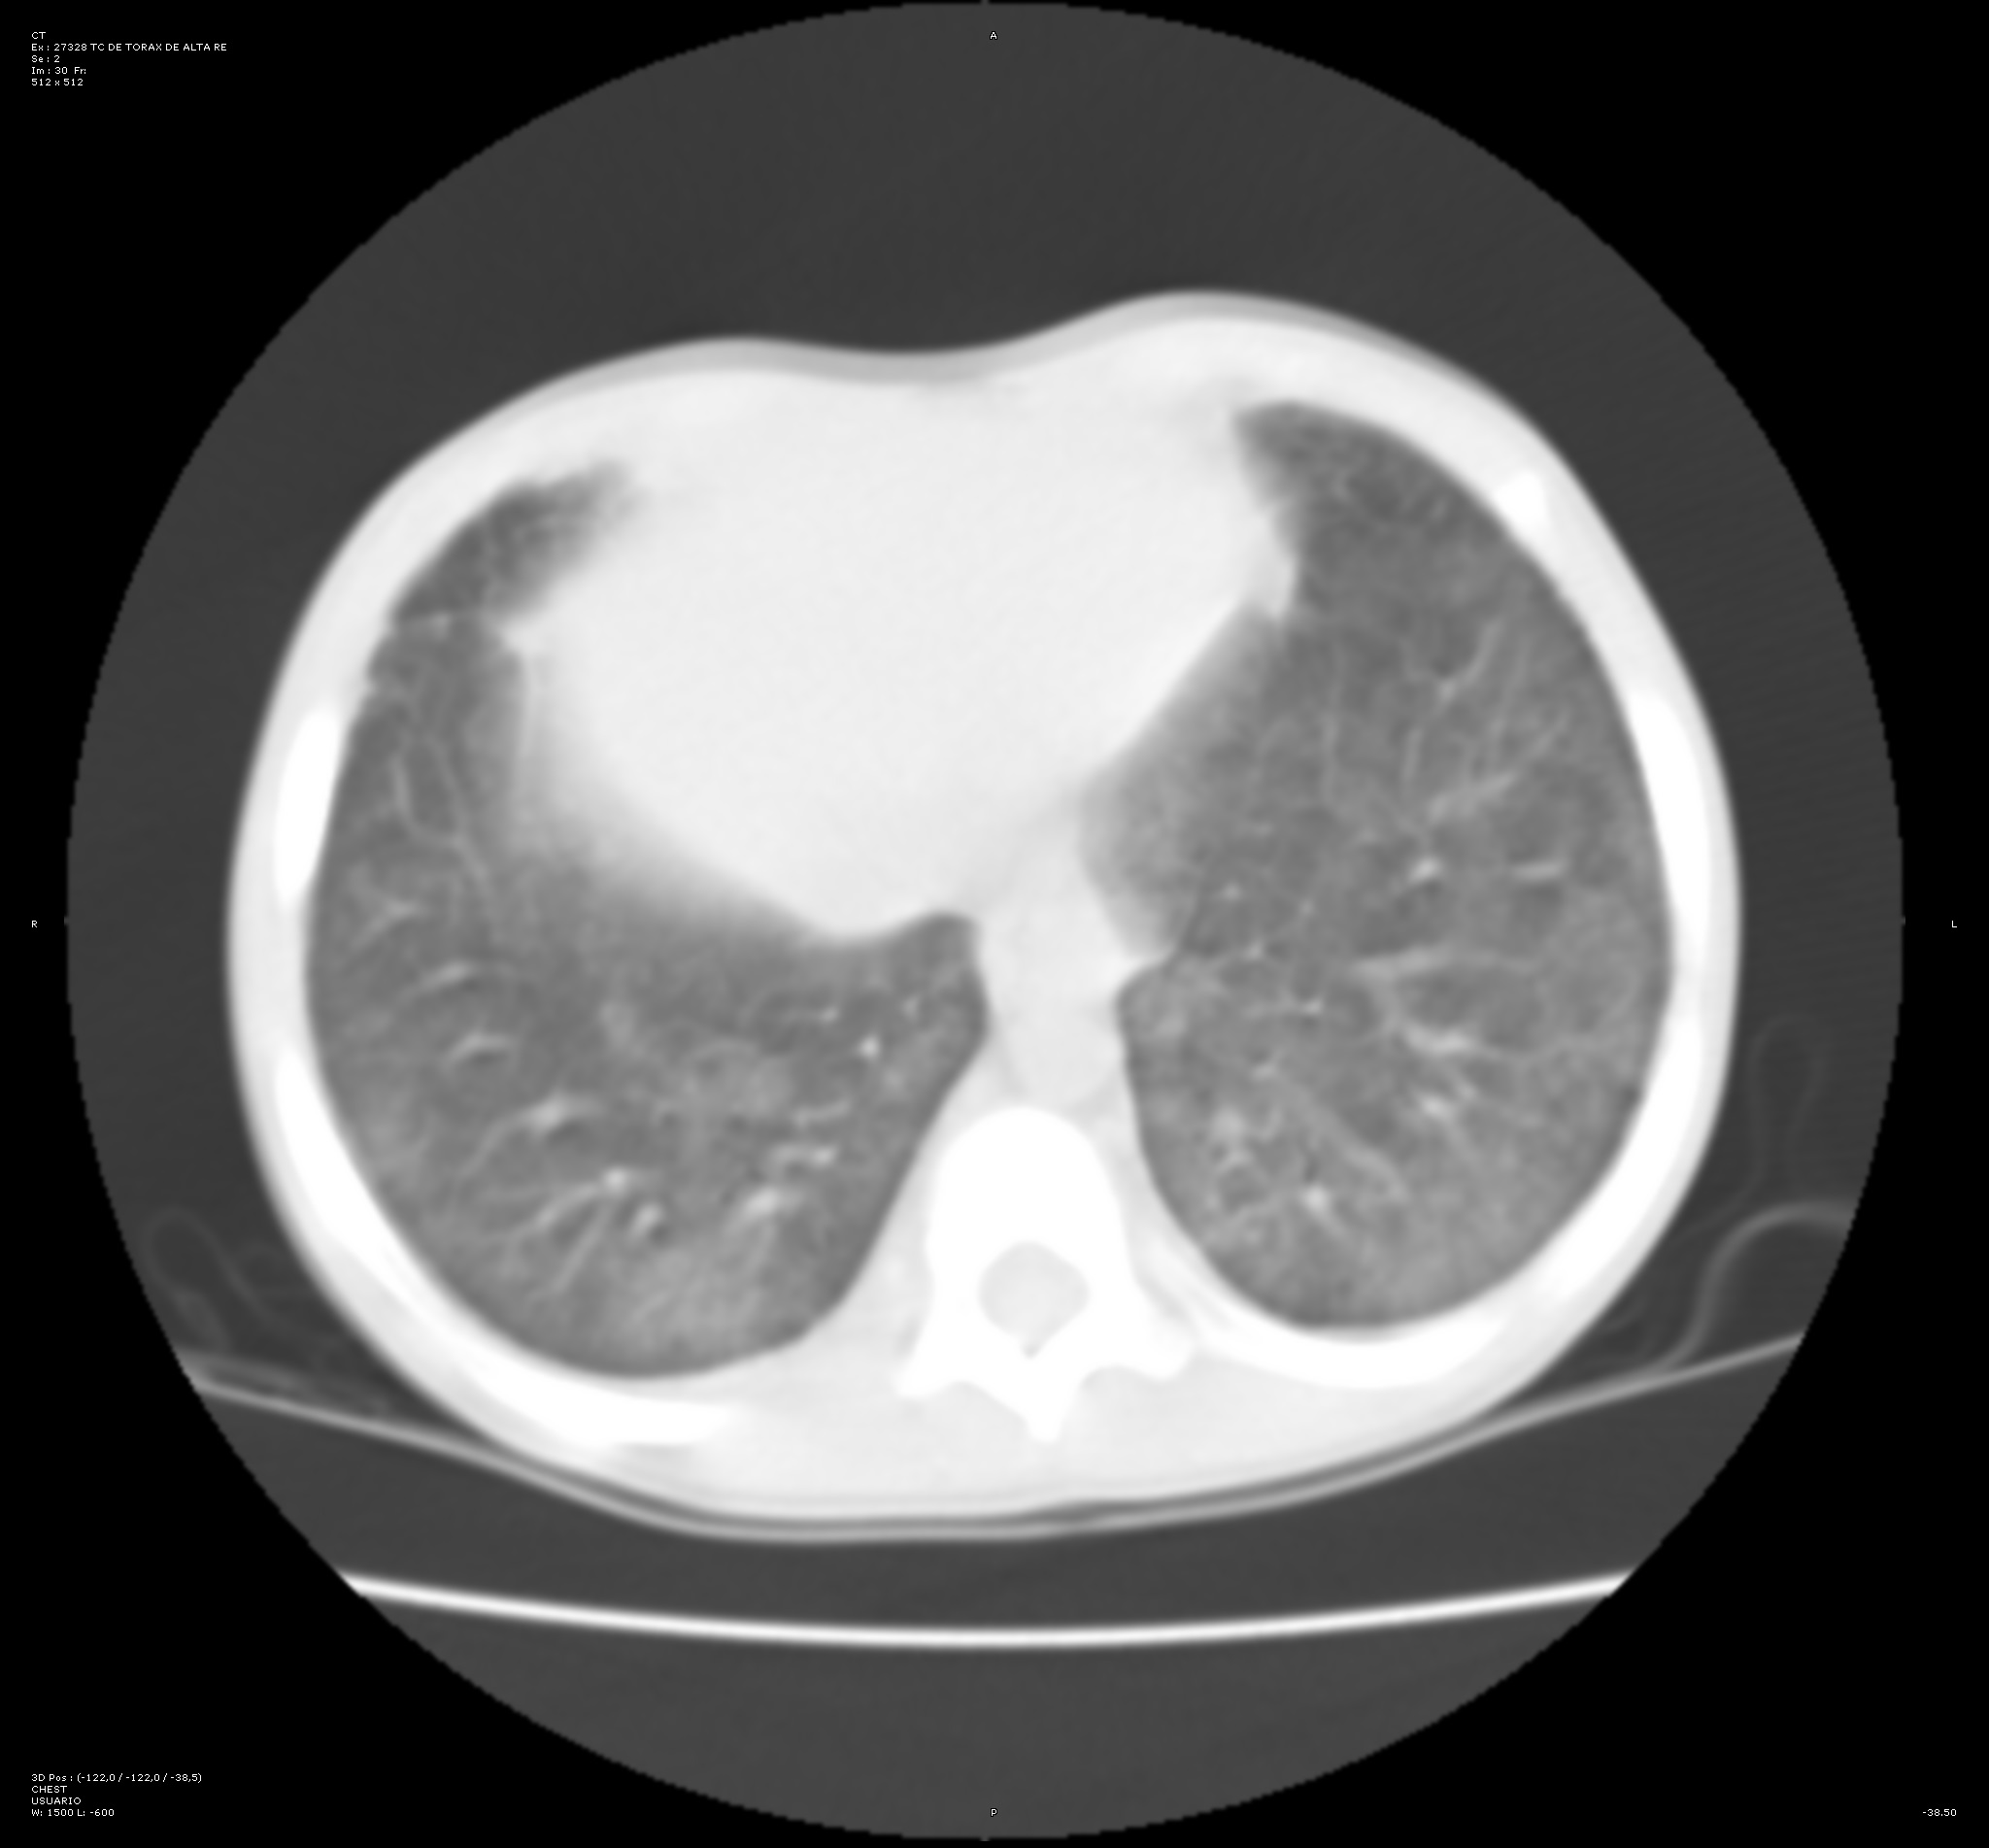

Con intención de no realizar en primer lugar una prueba invasiva que pudiera inestabilizar al paciente, se decide llevar a cabo una tomografía computarizada (TC) de tórax. En esta prueba se visualizan opacidades bilaterales parcheadas y simétricas en vidrio deslustrado de predominio en campos posteriores y basales. Este hallazgo incrementa la sospecha de hemorragia alveolar difusa.